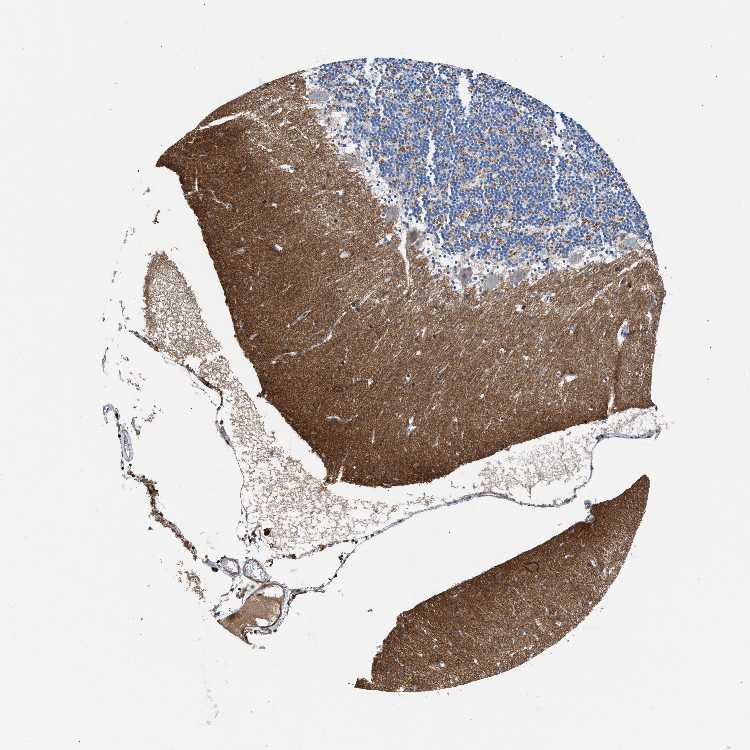

CEREBELLUM - Antibody stainingi

Antibody staining in the annotated cell types in the current human tissue is reported as not detected, low, medium, or high, based on conventional immunohistochemistry profiling in selected tissues. This score is based on the combination of the staining intensity and fraction of stained cells.

Each image is clickable and will lead to virtual microscopy that enables deeper exploration of all samples and also displays staining intensity scores, fraction scores and subcellular localization as well as patient and tissue information for each sample.

Antibody HPA016938

Purkinje cells Not detected

Cells in granular layer Low

Cells in molecular layer Not detected